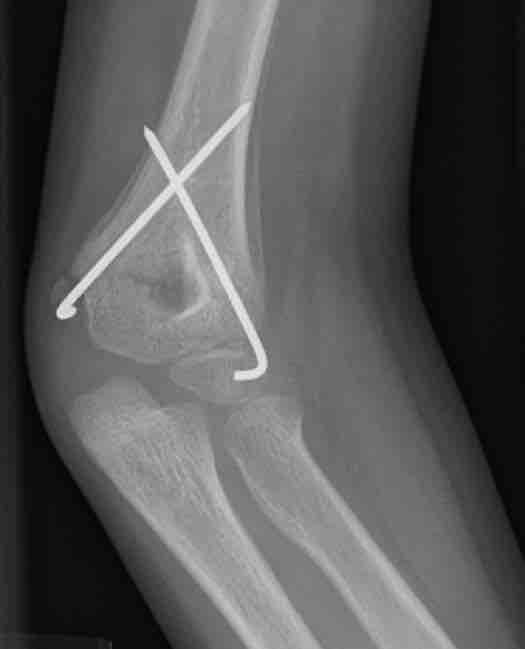

This figure depicts a radiograph of a child's healing supracondylar humeral fracture that has been treated with closed reduction and pinning. This image, taken three weeks post injury, demonstrates the benign periosteal reaction of normal healing bone.